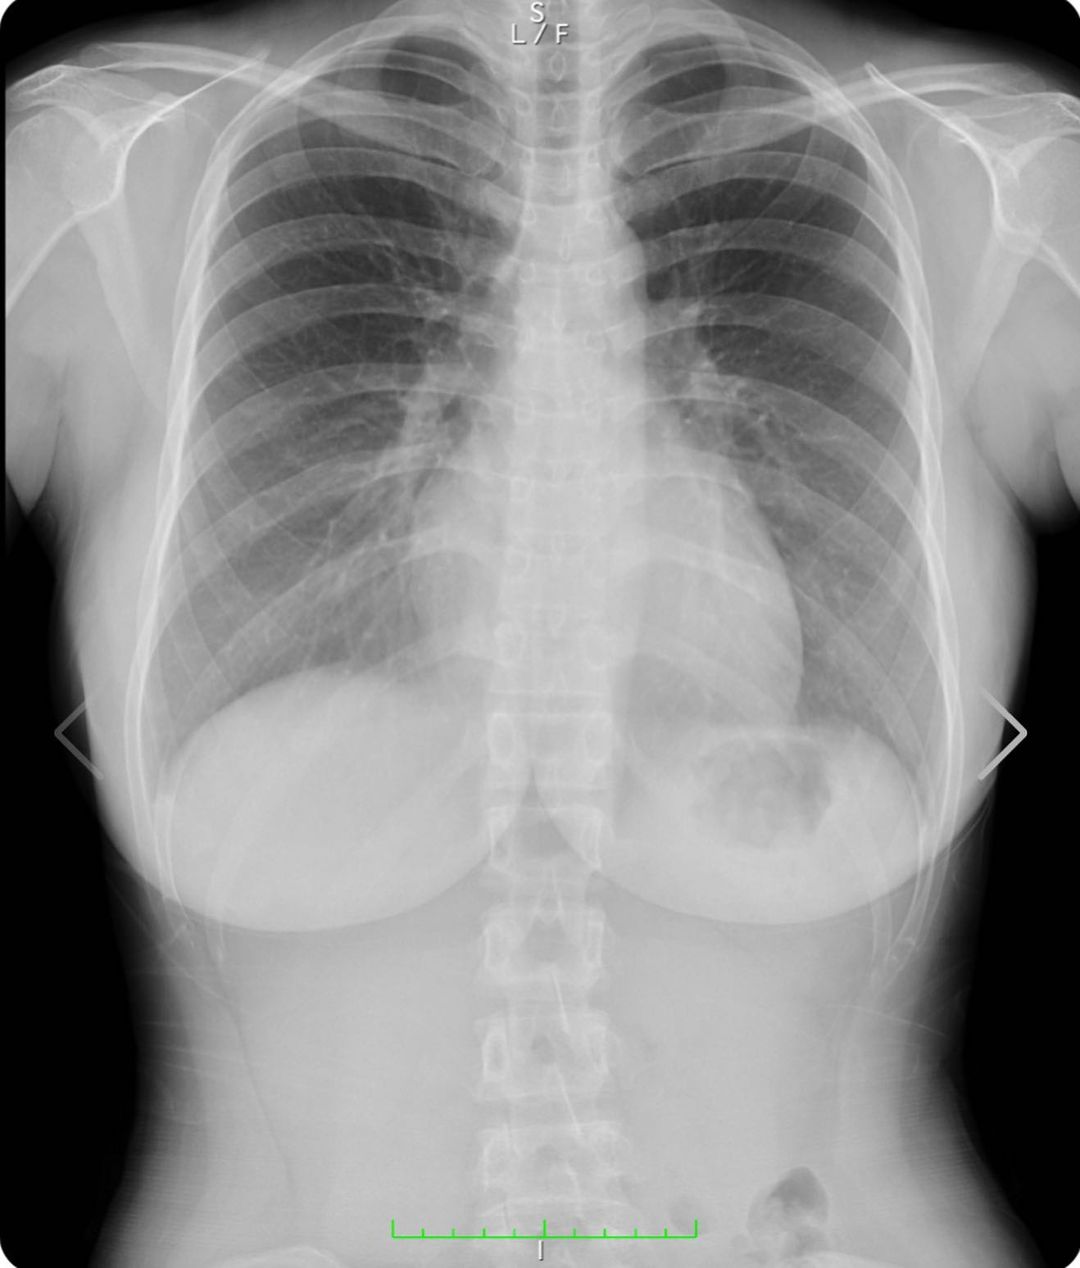

写真は私の胸部レントゲンです!www

正面から見た写真の

右の胸の黒いのは胃泡だよ安心してね